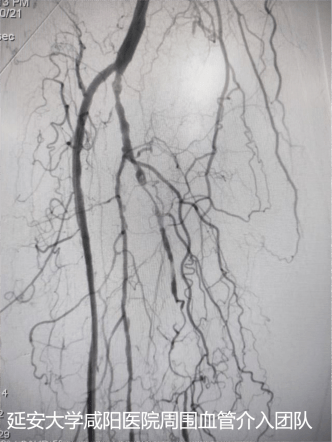

术后DSA